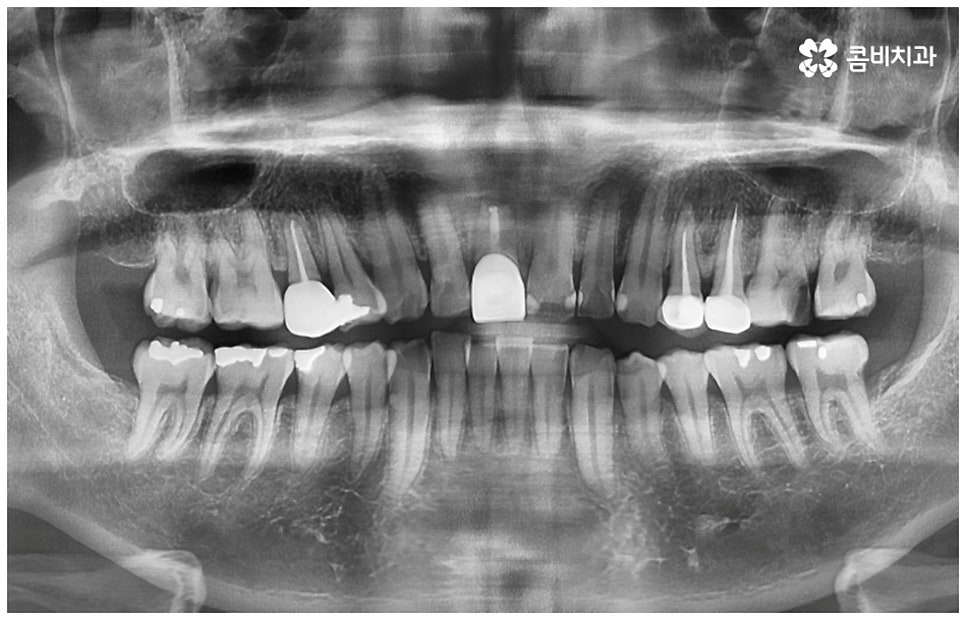

충치는 흔하게 발생하는 구강질환으로 한 번 생기면 자연적으로 낫지 않기 때문에 자신의 상황에 맞게 제 때 적합한 치료를 받는 것이 굉장히 중요한 포인트라고 할 수 있어요. 처음에는 별다른 증상이 느껴지지 않지만 시간이 지날수록 병증이 깊어지면서 내부까지 세균이 침투하여 감염이 일어나고 손상이 심해질 수 있는데요. 치아 겉면 일부만 손상될 정도의 초기 충치라면 보다 빠르고 간단한 레진 치료로 증상을 개선시킬 수 있으나 이 단계에서는 통증이 거의 없기 때문에 환자분들의 입장에서 모르고 지나치기 쉬우므로 주기적인 검진을 통해 초기 충치에 대처하실 필요가 있어요.

치아의 겉면인 법랑질은 우리 신체 조직 중에서 가장 단단하지만 내부로 들어갈수록 상아세관 다발이 모여있는 상아질, 그리고 신경과 혈관이 조밀하게 모여있는 연조직인 치수가 나오기 때문에 한 번 충치가 생기면 안쪽으로 악화되는 속도가 빨라질 수 있어서 치료 시기를 놓치지 않도록 주의하실 필요가 있어요. 또한 충치는 치료 후에도 관리를 제대로 해주지 않으면 재발하기 쉽기 때문에 일상 속에서 꼼꼼하게 양치질을 잘 해 주고 1년에 한 번 또는 두 번 정도 정기적으로 치과에 내원하셔서 위생 관리에 힘써 주시길 당부드리고 있어요.

여기서 어금니신경치료 란 법랑질과 상아질을 지나 치아 안쪽 깊은 곳의 치수 조직까지 감염이 되었을 때 손상 부위를 모두 제거하고 치근관을 소독, 밀폐하는 치료를 의미하고 있는데요. 사람의 치신경은 아주 얇고 치근관의 모양과 개수는 모두 다 다른데 만약 끝이 구부러져 있거나 미세 부근관이 여러 갈래로 많이 퍼져 있는 경우, 신경관이 막힌 경우라면 신경을 제거할 때 난이도가 올라가므로 더욱 주의깊게 치료할 필요가 있어요.

어금니는 위치상 구강 내 가장 안쪽에 위치하므로 평상시 양치질을 잘 해 준다고 해도 음식물 찌꺼기가 남아있을 가능성이 커 충치 발생률이 높은 치아라고 할 수 있는데요. 이렇게 충치로 인한 손상 때문이 아닌 다른 이유로 어금니신경치료 를 진행해야 하는 경우도 있을 수 있어요. 예를 들어 20살 전후로 사랑니가 나오면서 삐뚤어지거나 일부가 매복된 채로 비정상적인 맹출을 하게 되면 앞의 어금니 뿌리에 압박을 주는 등 좋지 않은 영향을 줄 수 있는데요. 이 때 바로 사랑니를 발치하지 않고 그대로 방치한 채 시간이 오래 흘러 어금니까지 손상이 생겼을 경우 어금니신경치료 를 받아야 할 수 있어요. 그밖에도 외부에서 큰 충격을 받아 어금니가 깨지거나 부러져서 드물게 신경이 노출된 경우에도 감염된 신경 제거가 필요할 수 있는데요.